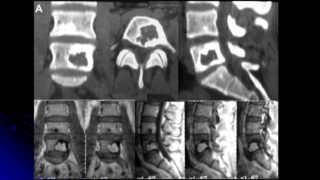

Контрольная КТ после вертебропластики позвонка, костный цемент обозначен красной стрелкой нажми на картинку для увеличения